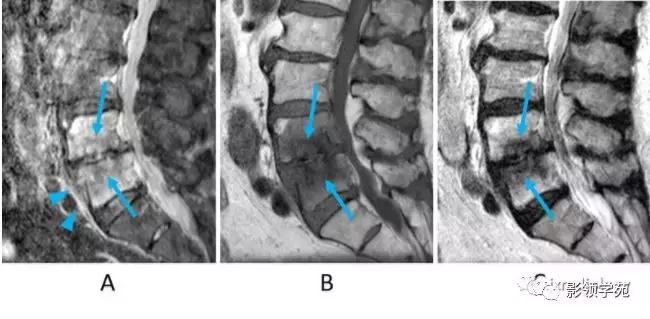

图2:急性椎体骨折(楔形压缩骨折)。A:STIR矢状面图像,B:T1WI矢状面图像,C:T2WI矢状面图像。女,70岁。下胸椎椎体呈楔形改变。STIR(A)骨髓信号强度高,T1WI低(B),T2WI混合信号强度(C)。每个序列在椎体中显示低信号强度线,反映压缩的小梁(A,B,C箭头)。